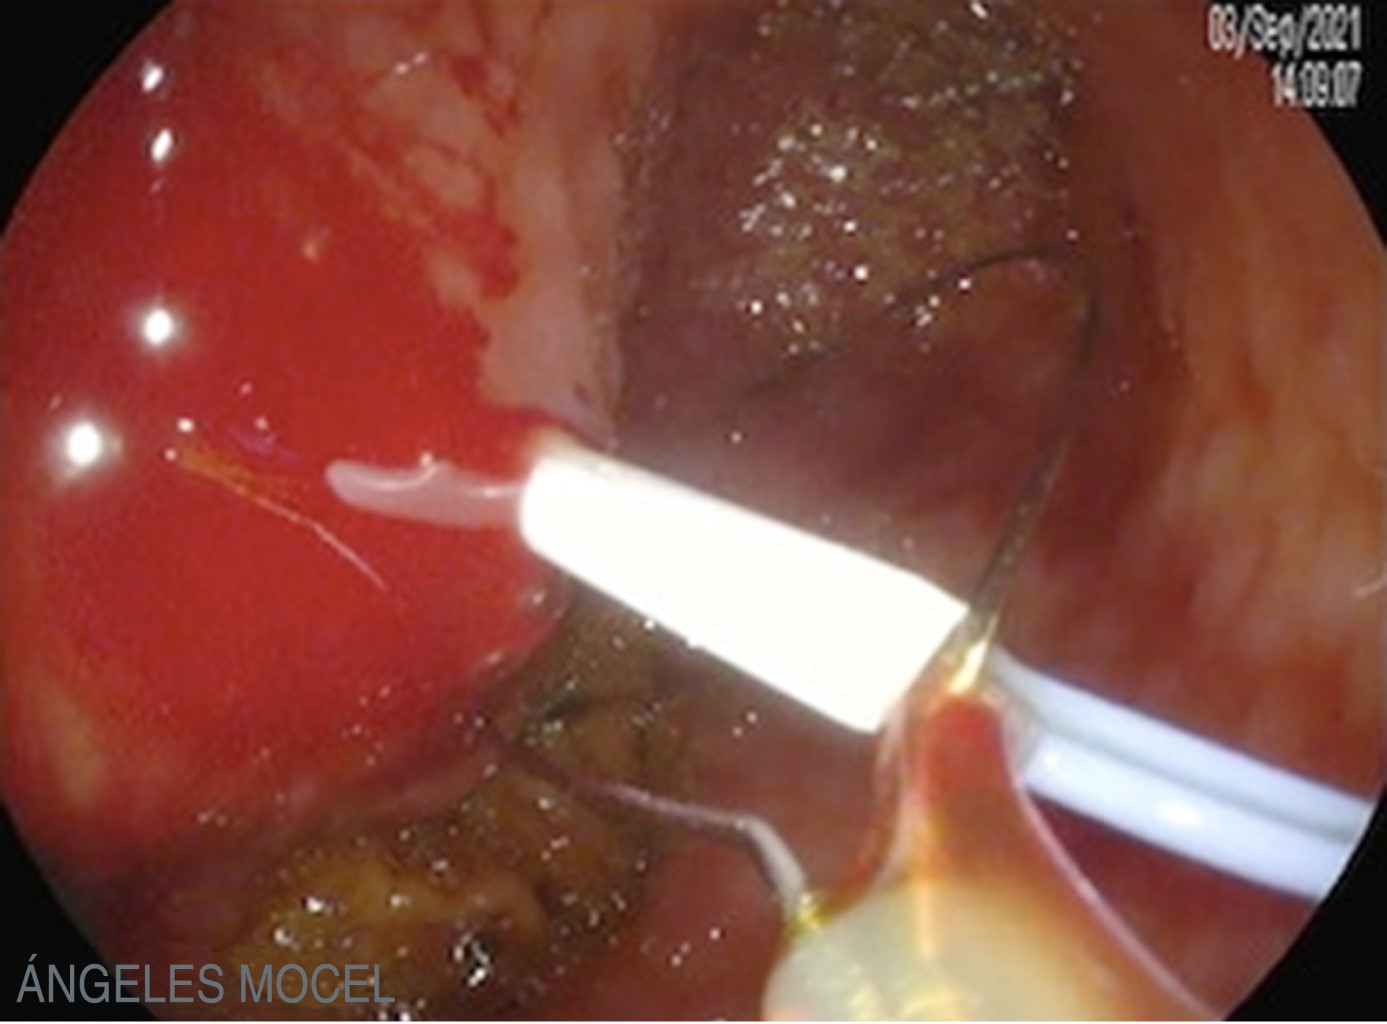

Figure 1